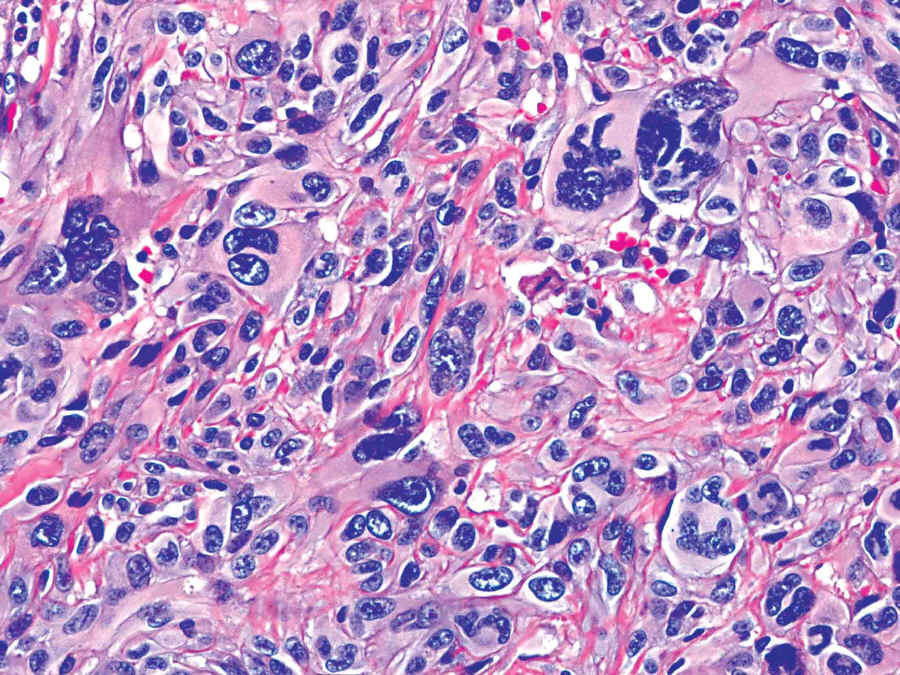

Case #3

81 year old man with a 2 cm red nodule in the skin of the face.